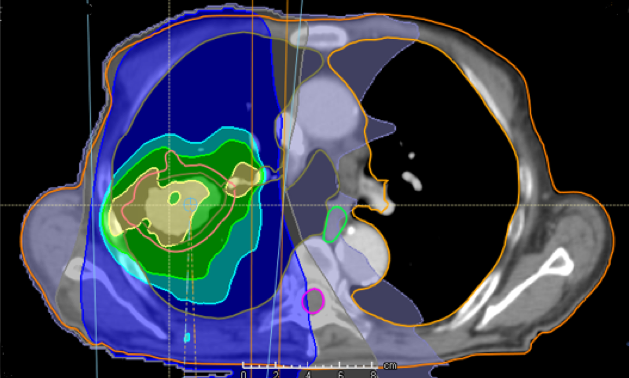

Proton therapy is a technologically advanced treatment modality that uses a beam of high-energy protons to irradiate the tissue. Compared to the conventional photon-based radiotherapy the proton therapy benefits from delivering a more precise radiation dose with lower dose to surrounding critical organs (see figure). In Norway we will soon get two proton therapy centers both for treatment of patients and for research.

Treatment with photons

Treatment plan with protons

Figure: Example on difference in radiation dose distribution in photon-based radiotherapy and proton therapy for patient with lung cancer.